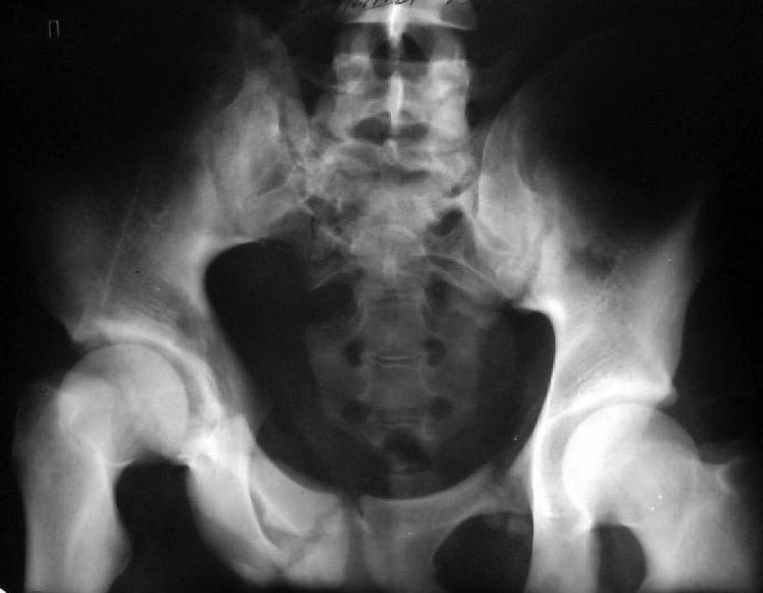

Застарелый перелом таза

Уважаемые коллеги! Хотел-бы обсудить варианты лечения больной с застарелым переломом таза. Возраст 40 лет. Травма 11 месяцев назад. Главный травматолог Камчатского Военно-морского госпиталя Юрий Алексеевич Булахтин

У больного судя по всему вертикальная деформация таза. А каковы основные жалобы пациента и какие у него функциональные требования?

Для принятия решения об оперативном лечении и о его объеме, представляется целесообразным выполнение рентгенографии в проекции "inlet", а так же функциональных рентгенограмм стоя попеременно на правой и левой нижних конечностях (для определения нестабильности тазового кольца).

Мы, как правило, в подобных случаях проводим оперативное лечение в несколько этапов. Первым устраняем деформацию при помощи АВФ (кольцевой конструкции с фиксацией задних отделов), вторым- выполняем введение илиосакралых винтов, накостный остеосинтез передних отделов.

Для информации к размышлению о возможности исправления имеющейся деформации предлагаю похожий случай.